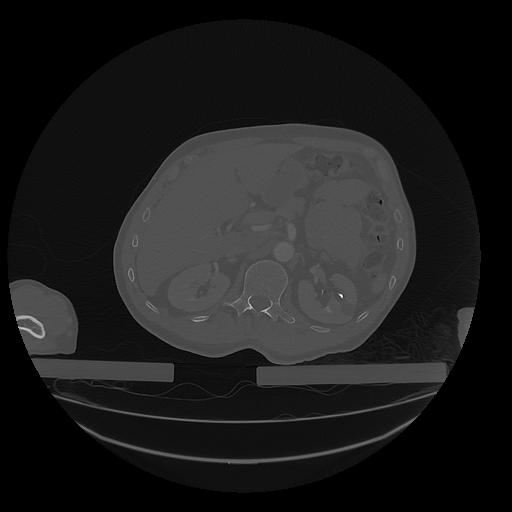

31 PULMON,CE,Vol,1.0,PULMON,,